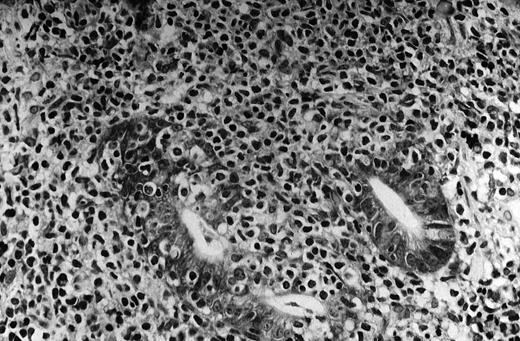

The pivotal feature of low-grade MALT lymphoma is the presence of a variable number of lymphoepithelial lesions that can be defined as unequivocal invasion and partial destruction of gastric glands or crypts by aggregates of tumor cells (Figure1). Lymphoepithelial lesions are of striking relevance for the diagnosis of low-grade gastric MALT lymphoma; however, they can sometimes be seen in the context of florid chronic gastritis and can also be present in other sites of both native and acquired MALT.88 89

The neoplastic lymphocytes infiltrate some residual gastric glands, giving rise to lymphoepithelial lesions (Giemsa staining, × 512, courtesy of Prof Stefano Pileri, University of Bologna, Italy).